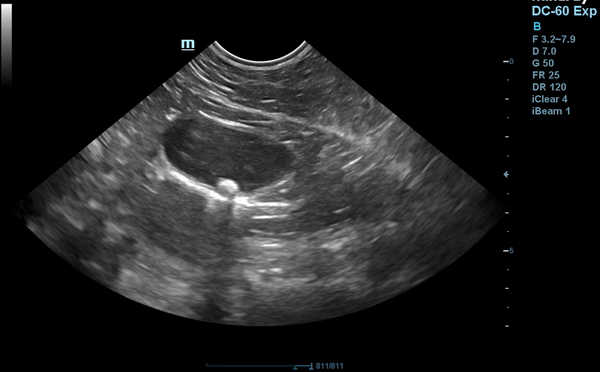

Tiger ist inzwischen ein 17-jähriger Europäisch-Kurzhaar-Kater. Letztes Jahr wurde er uns im Sommer wegen chronischer Magen-Darm-Beschwerden und Gewichtsverlusts vorgestellt. Trotz seines Alters scheuten seine Besitzer keine Kosten und Mühen. Im Ultraschall zeigten sich eine verdickte Darmwände, besonders die Muskelschicht war sehr dick (rote Markierung). Um der Ursache auf den Grund zu gehen, entnahmen wir Gewebeproben. Von dem Eingriff erholte sich Tiger sehr gut und die Wunden heilten ab.

Leider ergaben die Proben, dass es sich um einen Tumor handelte.

Aber Tigers Besitzer waren wieder bereit, alles für Tiger zu tun. Er bekommt seitdem eine Chemotherapie in Tablettenform und Kortison gegen die Entzündung.

Nun war Tiger zu einer Kontrolluntersuchung bei uns und es geht ihm blendend.

Im Ultraschall ist deutlich zu sehen, dass die Darmwand nicht mehr verdickt und der Tumor unter Therapie derzeit unter Kontrolle ist.